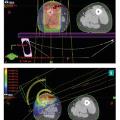

Radiothérapie dans le traitement des sarcomes

Depuis les années 1980, la chirurgie conservatrice suivie d’une radiothérapie postopératoire est devenue le standard thérapeutique pour la plupart des sarcomes des tissus mous des membres.1,2 Le bénéfice de l’association radio-chirurgicale est surtout observé chez des patients avec des tumeurs de haut grade, de localisation profonde…